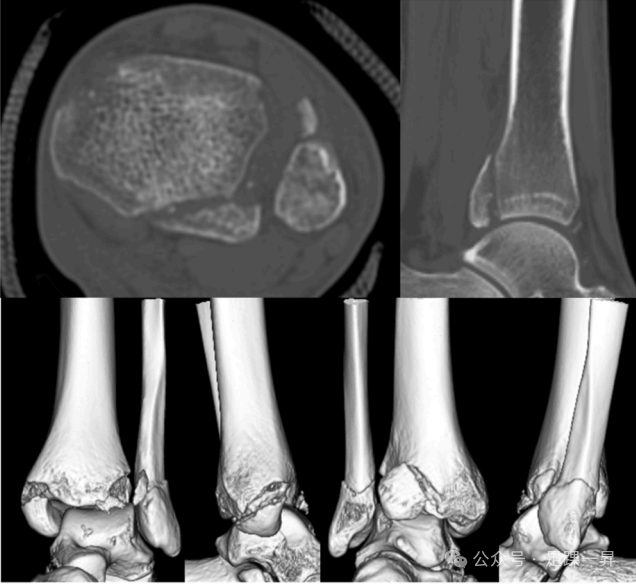

图片

图示Mason和Molloy 1型后踝骨折块。(A)伴有LD型移位的1型:提示PITFL深层断裂。(B)无LD型移位的1型:提示PITFL深层保留。